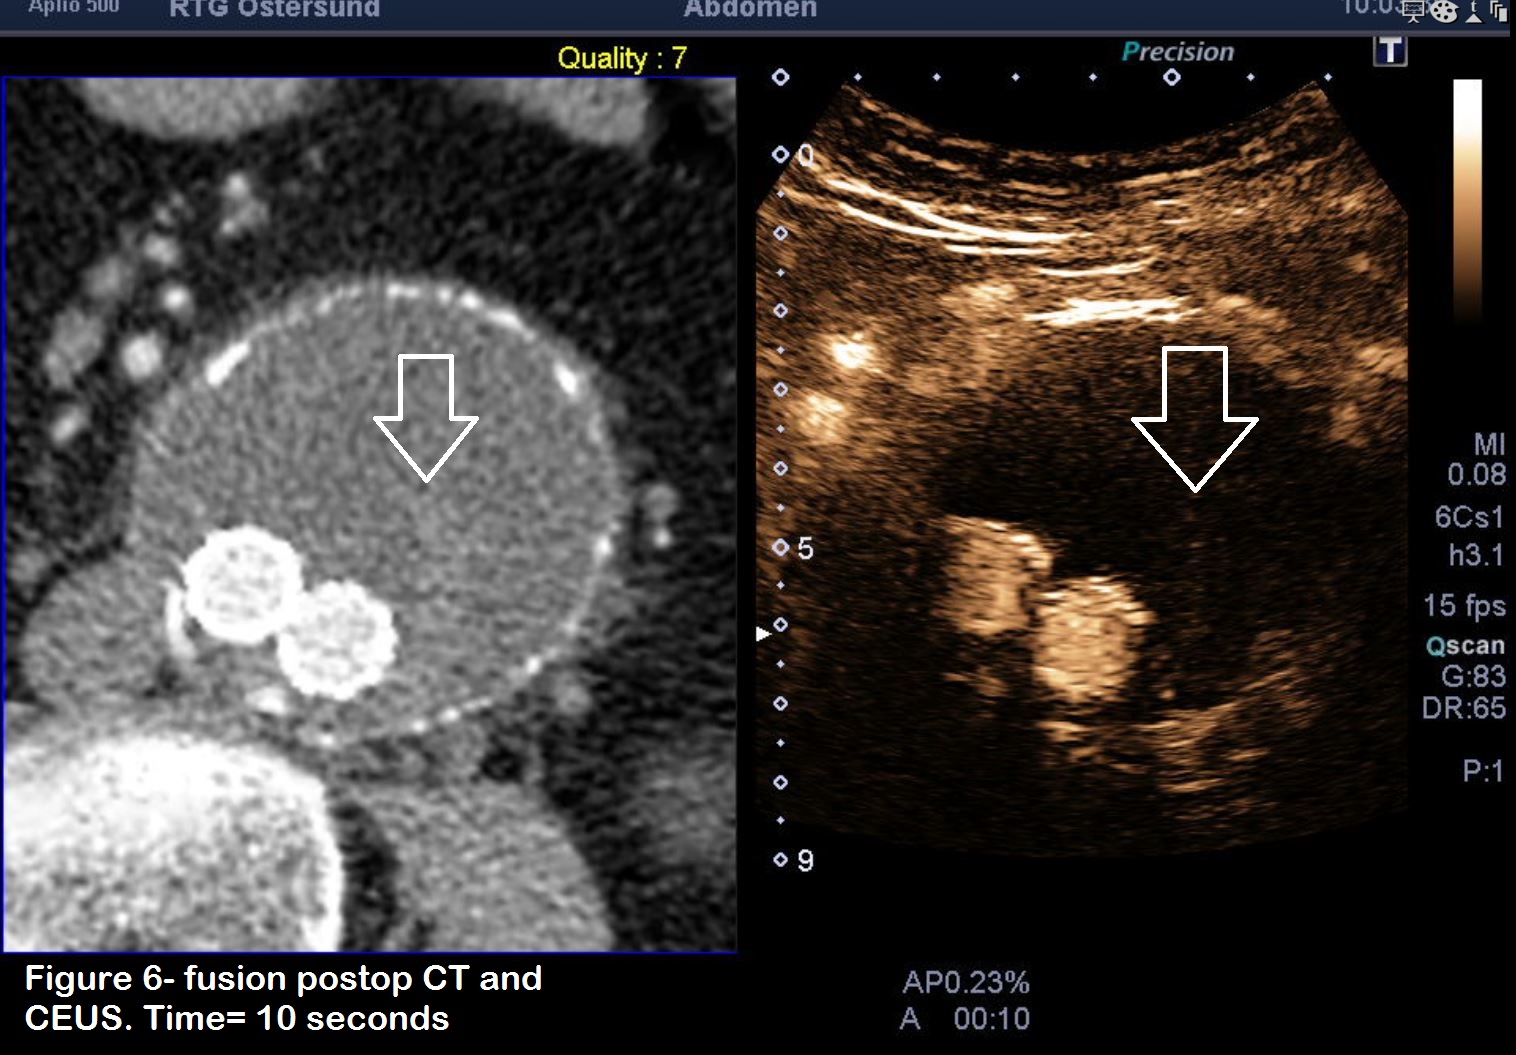

Figures 6 & 7: Two further injections of contrast with images focused lower down in the stent graft, where there was Doppler flow in the stent. Note the time difference where the first passage of contrast through the graft (figure 6) occurs at 10 seconds after injection, but the endoleakage only appears after 19 seconds. There is thus a delay of nine seconds which is a strong indicator that this is a type 2 endoleak. (time is shown at the bottom of the picture, A = seconds after injection).